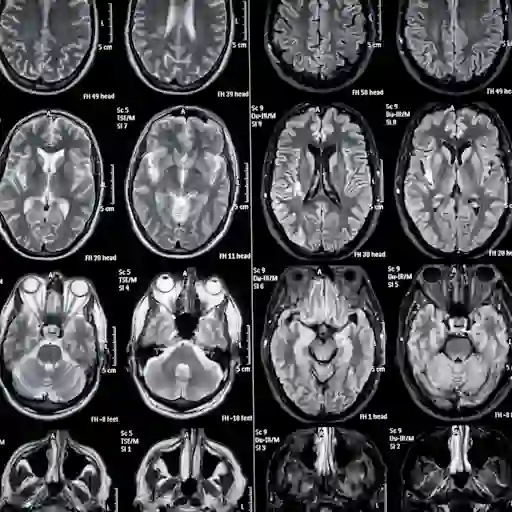

病变或斑块

女士最使用的条件之一是病变,给博士说。例如,你可能会听到后MRI,你对你的大脑有损伤,可听起来可怕。“我告诉人们一个病变就意味着有什么不应该,但它经常像一个雀斑,不是肿瘤,”她补充道。是否指病变或斑块,这些通常发生在大脑和脊髓的部分的保护鞘神经,称为髓,已经被一扫而光,引起神经损伤。